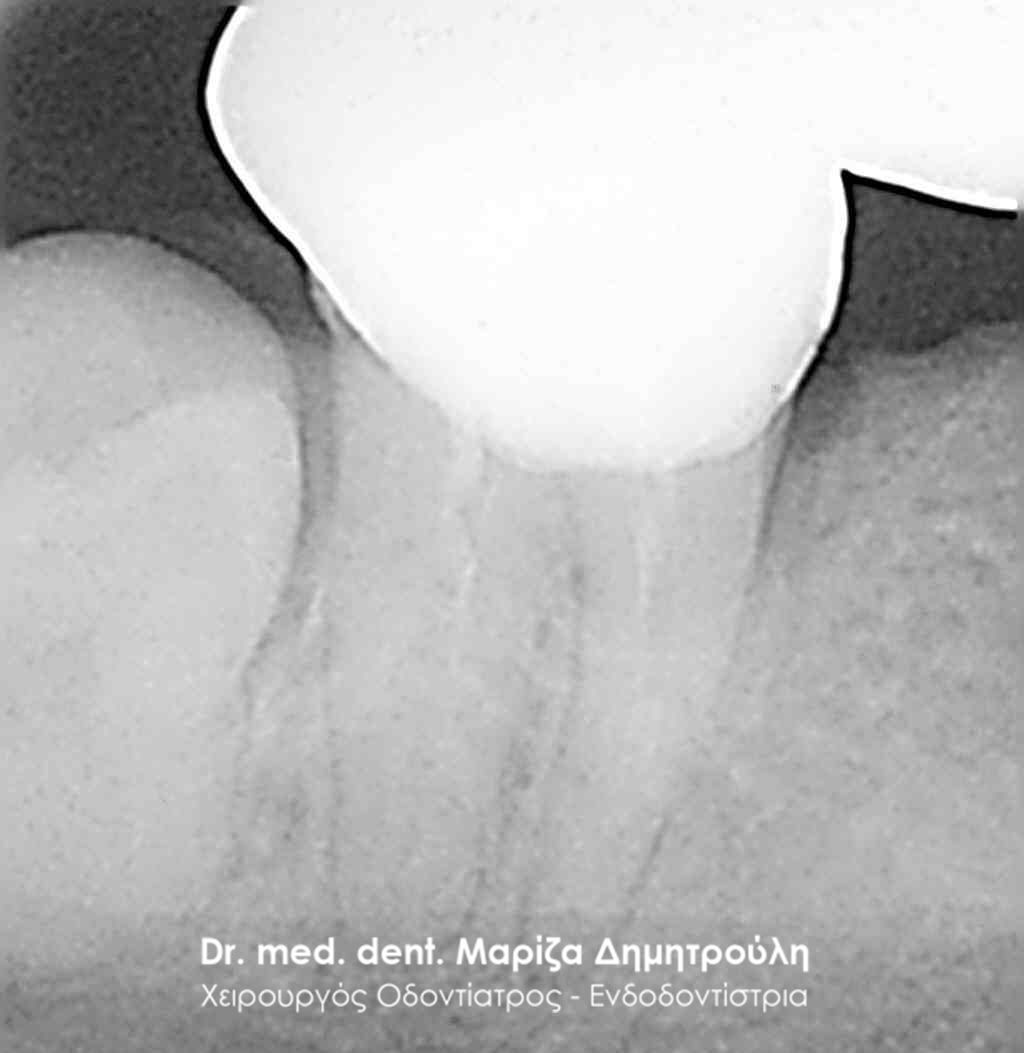

Clinical photo after the root canal filling